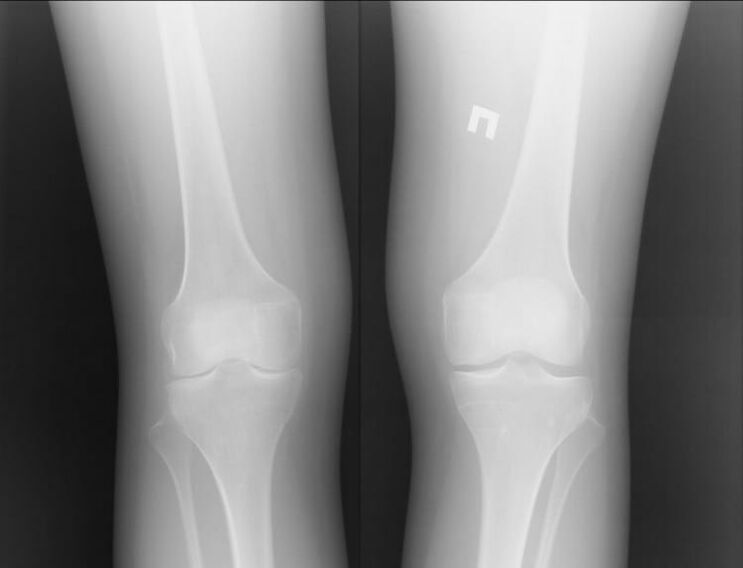

Arthrose ist eine Gelenkerkrankung, die durch Knorpelprobleme verursacht wird. Sie beginnen sich allmählich aufzulösen und zu brechen, was entsetzliche Schmerzen verursacht. Es tritt sowohl akut als auch langfristig auf. Es tritt normalerweise morgens oder nach intensiver körperlicher Aktivität auf.

Gelenkarthritis ist eine Erkrankung der Gelenke. Es äußert sich hauptsächlich in Schwellungen und Rötungen. Die Gelenkinnenhaut wird zerstört, was oft schwer erträgliche Schmerzen verursacht.

Beide Krankheiten haben in ihrem Namen „Arthron“ eine gemeinsame Wurzel. Wenn man es aus dem Griechischen übersetzt, erhält man „set“. Beide Erkrankungen gehen mit Gelenkbeschwerden und Schmerzen einher. Solche Pathologien treten bei akuten negativen Empfindungen und Beschwerden auf. Verletzungen der Knorpelschicht schränken die Bewegung ein und erschweren sie.

Arthrose und Arthritis verändern den gewohnten Lebensstil des Patienten. Es wird schwierig, sich zu bewegen, es treten Schmerzen auf und der Widerstand lässt nach – das sind die Hauptsymptome. Allerdings entwickelt sich jede dieser Krankheiten nach ihrem eigenen Szenario.